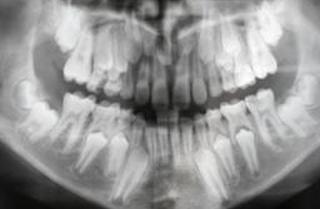

Бруксизм во сне — это расстройство, которое включает в себя движения в челюсти и скрежетание зубами. Вы можете распознать симптомы расстройства сна, если испытываете:

- Зубы сглажены, имеют сколы или трещины